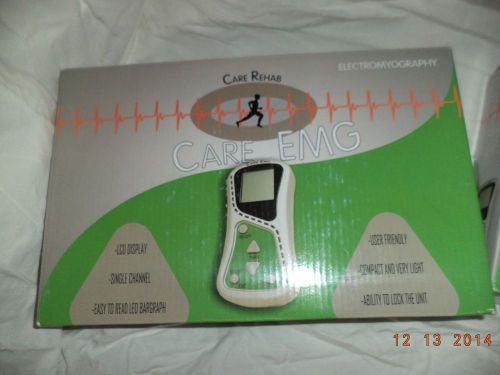

CARE REHAB Single Channel EMG Electromyography & TENS, EMS Electrodes